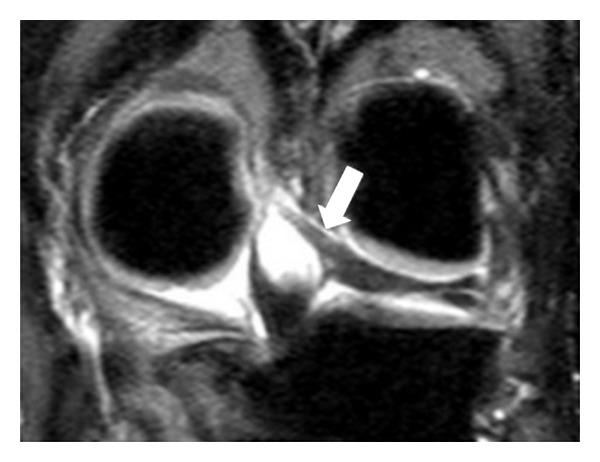

前后半月板股骨韧带:磁共振成像评估

Anterior and posterior meniscofemoral ligaments: MRI evaluation.

Although meniscofemoral ligaments are distinct anatomic units, their anatomy and function are controversial from an anatomic and radiologic point of view. Five hundred knee MR examinations were retrospectively studied in an effort to demonstrate the incidence and variations regarding sex and age distribution, as well as the anatomy of the meniscofemoral ligament at magnetic resonance imaging. Patients were mostly men, three hundred and twelve, in contrast with women who were fewer, one hundred eighty-eight patients. The mean age of the patients who were included in this study was 46 years. More than half of them were between 20 and 40 years old; one hundred thirty-three patients among 20 to 30 years old and one hundred and one patients among 31 and 40 years old, in total two hundred thirty-four patients.

虽然半月板股骨韧带是独特的解剖结构,但从解剖学和放射学角度来看,它们的解剖结构和功能仍存在争议。我们回顾性研究了500例膝关节磁共振成像(MR)检查,以阐明半月板股骨韧带在性别、年龄分布方面的发生率和变异情况,以及其在磁共振成像中的解剖结构。患者以男性居多,共312例,女性较少,为188例。纳入本研究的患者平均年龄为46岁。其中一半以上患者年龄在20至40岁之间;20至30岁的患者有133例,31至40岁的患者有101例,总计234例。